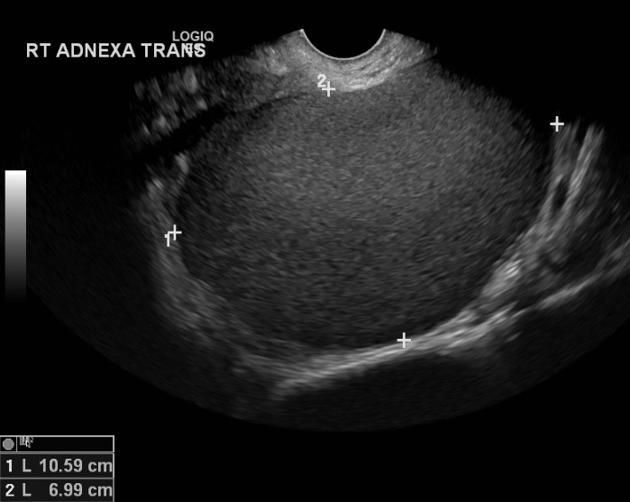

Localização mais comum: ovariana (endometrioma)

USG: endometrioma // RNM: nódulos

Endometrioma (cisto de chocolate)

Endometrioma: cistectomia